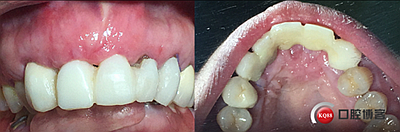

患者女性,52歲,缺失三顆牙,骨性前突,頜弓窄,身高175,魁梧,放了三顆牙是不是有點(diǎn)細(xì)?左上3開膠了,牙體有腐蝕。

鄰牙重新備牙,制作臨時(shí)樹脂橋體,缺牙區(qū)三顆變?yōu)閮深w。下圖是術(shù)后一個(gè)月口內(nèi)照。

大家看看前后對(duì)比,效果不錯(cuò)。